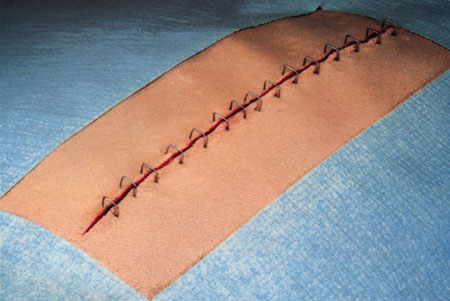

Staples

Staples are less reactive than the least reactive suture. Deeply implanted staples do not affect tissue defenses, although staple cross members that are flush with the skin can produce cross-hatched scarring. The development of disposable staplers with absorbable tacks obviates the need for removal of staples. Subcuticular closure of skin is now also possible through the use of a disposable stapler that uses twin gripper blades to approximate and evert the wound edges and insert a disposable pin into the dermis